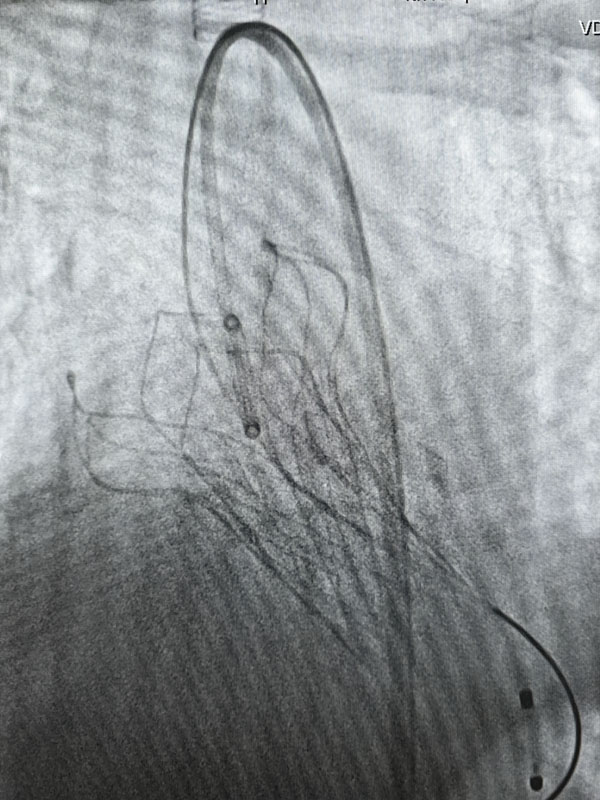

经过充分的术前准备,两台手术由心血管外科赵永波副主任主刀,赵伟超主治医师、侯五辉主治医师密切配合,选择经皮股动脉穿刺,预埋缝合器,术中反复造影,准确定位释放瓣膜,术后造影及超声提示人工瓣膜开启功能良好。为确保术中安全,体外循环小组全程保驾护航。患者生命体征平稳,术后一日均转出监护室。